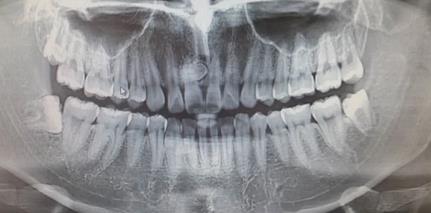

在临床上通常会出现牙龈鼓包硬硬的状态,此情况都是由于牙齿增生所导致的,但出现牙齿增生时大家都比较恐惧,尤其比较关注牙齿增生的治疗方式。那么牙齿增生怎么治疗?

牙齿增生治疗方式取决于诱发牙齿增生的诱因。如果是存在慢性牙龈炎,可以请到专业医院进行超声波洗牙,减少牙龈炎症,在洗牙之后牙齿增生就会逐渐缓解。如果这些属于药物性牙龈增生,则在停用导致牙龈炎症的药物以后就会有所缓解。对于这些比较严重的牙龈增生患者,可以去专业口腔科进行牙龈切除术。

导致牙齿增生的因素有很多,日常生活中比较常见的是年龄增加、自身骨质疏松,以及日常生活中用牙不恰当等因素。其次还与日常生活中的口腔清洁卫生有关,另外如果自身患有牙龈病或者是牙周炎等牙周疾病等患者也会存在牙齿增生。总之诱发牙齿增生的因素有很多,建议大家日常生活中注意口腔清洁,保持良好习惯。

牙齿增生可能会无限增长,出现牙齿增生主要是由于炎症的刺激以及外伤和遗传的因素所导致,如果及时没有处理,有可能会导致牙齿增生加重。所以在日常生活中尽量做好口腔的护理,定时漱口刷牙,在餐后一定要漱口,避免食物残留在牙缝中,日常饮食不能吃辛辣刺激性的食物,以免加重牙齿增生的现象。平时还需要多注意补充新鲜蔬果,以此弥补身体所需营养。必要时前往医院进行治疗,建议在治疗期间前往正规医院,通过手术方式将其切除,积极与医生进行沟通,避免牙齿增生无限增长。